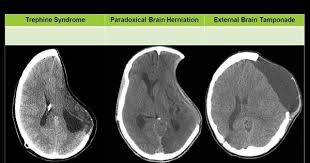

Mount Fuji Sign Is Seen On Cross Sectional Imaging And Implies Tension Pneumocephalus Is Present The Sign Refers To Radiology Frontal Lobe Medical Education